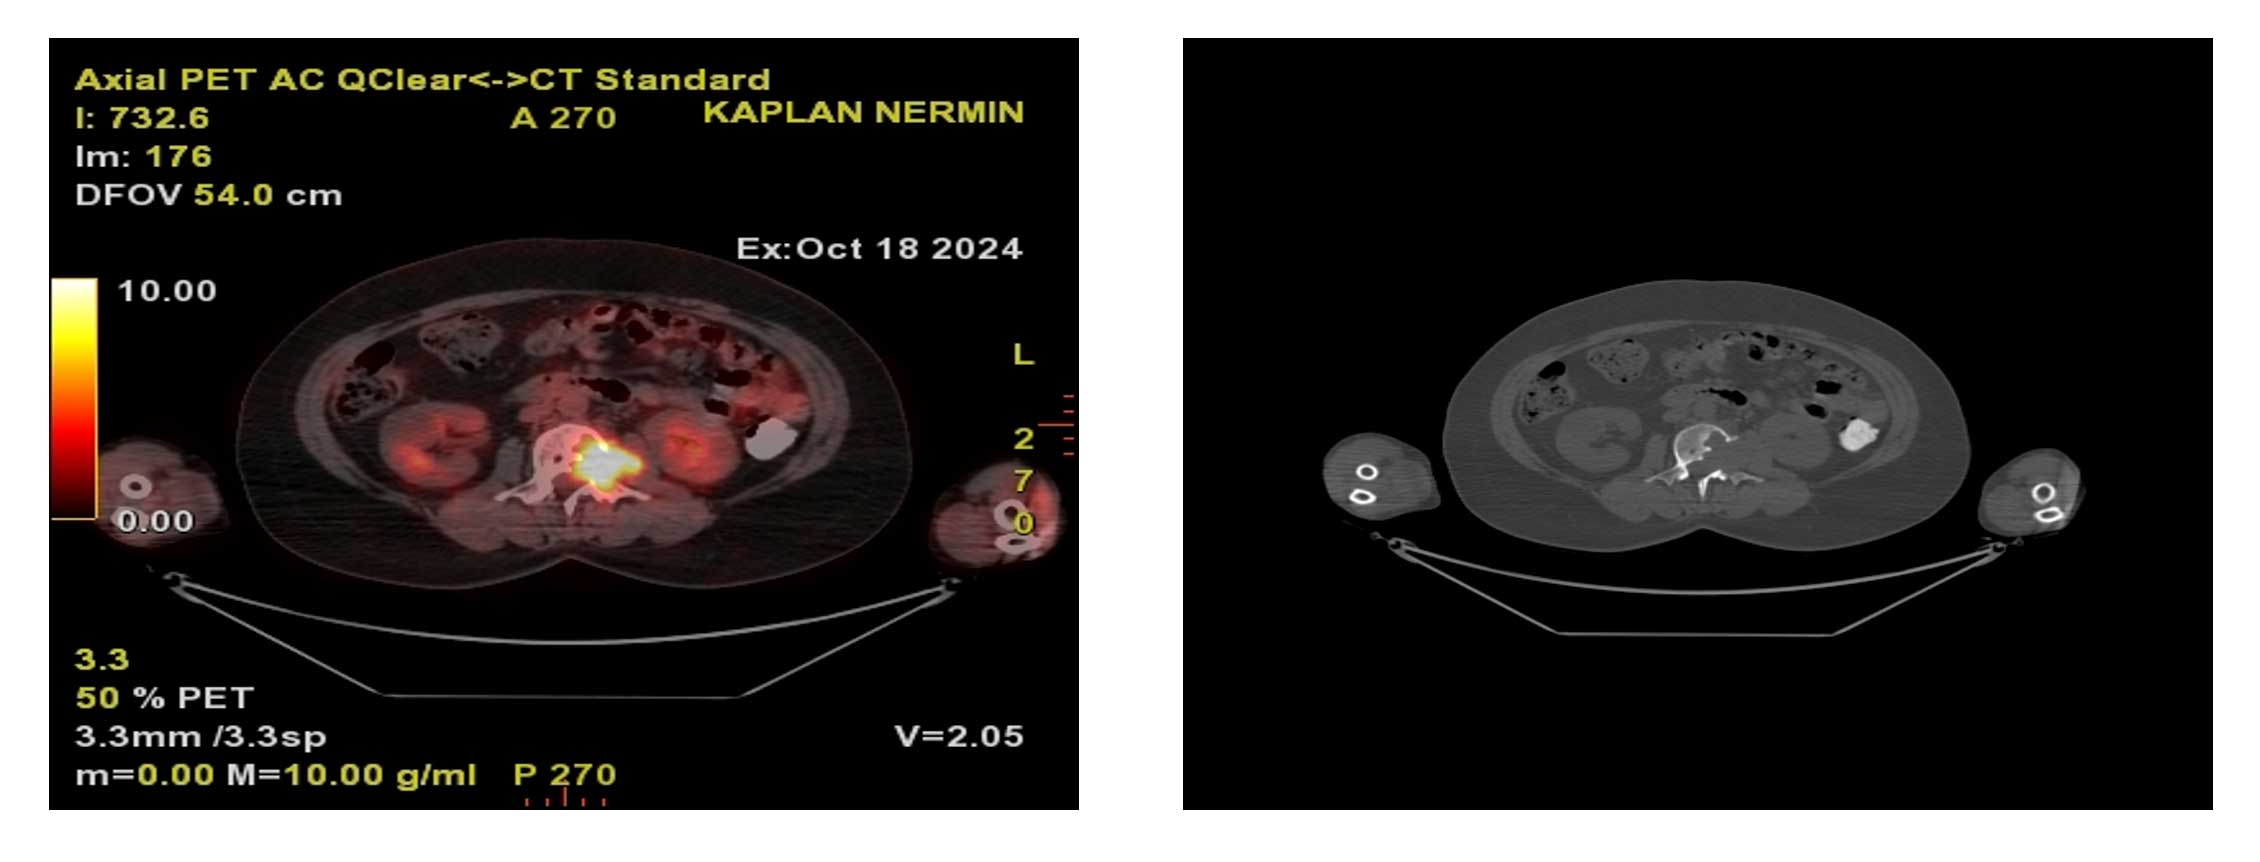

Ameliyat Öncesi: PET-CT’de artmış aktivite ve kemikte harabiyet görülmekte.